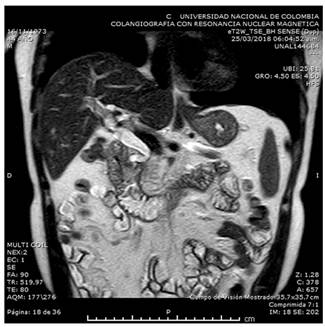

Las lesiones quísticas en el surco o en la pared duodenal, son más evidentes en la secuencia T2 y es frecuente ver un aumento del grosor o estenosis de la pared duodenal. El colédoco puede presentar estenosis variable. En la forma segmentaria, la cabeza o el páncreas entero pueden verse hipointensos en la secuencia T1, con atrofia del parénquima y dilatación ductal, mostrando la pérdida progresiva de células glandulares que son reemplazadas por tejido fibroso 29,35. La CPRE informa la relación entre el sistema ductal y los cambios quísticos. En la mayoría de los casos se encuentra un ensanchamiento del espacio entre los conductos pancreáticos, colédoco distal y la luz duodenal, por la lesión ocupante de espacio en el surco, así como un marcado engrosamiento de la pared duodenal 28. La colangiorresonancia de nuestro paciente mostró dilatación de la vía biliar, producida por el importante edema en la región peripapilar (Figura 4).